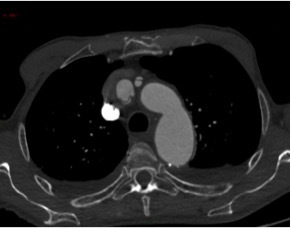

Un angioscanner thoraco-abdomino-pelvien est donc réalisé. Les Figures 11, 12, 13, 14 et 15 présentent des reformations axiales issues de celui-ci.

Question 7 : Concernant les structures légendées, quelles sont la/les proposition(s) exacte(s) ?

Vrai chenal

Déchirure intimale, qui constitue la porte d’entrée de la dissection.

Artère carotide commune droite

Artère coronaire droite naissant du sinus de Vasalva

Visualisation de la déchirure intimale d’où nait le faux chenal, dans lequel la déchirure est éversée, au niveau de l’aorte ascendante, avec un flap intimal étendu au tronc artériel brachio-céphalique, à la carotide commune droite et à la carotide commune gauche. En revanche absence d’extension au sinus de Vasalva, à la coronaire droite.

Dissection aortique de type A selon Stanford avec porte d’entrée de l’aorte ascendante en amont du tronc artériel brachio-céphalique et extension aux troncs artériels supra-aortiques. Pas d’extension au sinus de Vasalva, aux coronaires ni à l’aorte descendante. Pas de signe de rupture intra-péricardique ou intra-médiastinale.

La présence d’un flap intimal est pathognomique de la dissection aortique.